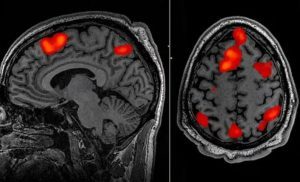

Un nuevo sistema de inteligencia artificial puede reconstruir los pensamientos de una persona con gran exactitud a partir del escaneo de su cerebro con fMRI.

Metidos cada uno en un escáner de resonancia magnética funcional, tres voluntarios escucharon pacientemente varias historias –en concreto, de un podcast famoso en Estados Unidos–. Mientras, un modelo de lenguaje (LLG, siglas en inglés de Large Language Model), el GPT-1, al que los investigadores se refieren como «descodificador«, iba analizando sus patrones de actividad cerebral en distintas regiones del córtex, buscando correlaciones entre esos datos y el contenido de los mensajes que estaban escuchando. Durante 16 horas –¡no seguidas!– entrenaron al programa para que fuera capaz de traducir la forma en que el cerebro reproducía las historias mientras las escuchaba.

En la siguiente fase del experimento, los voluntarios escuchaban una nueva historia, también dentro del escáner, mientras el decodificador iba generando texto solo a partir de la actividad cerebral registrada por las imágenes neuronales. El éxito fue sorprendente: alrededor del 50% de las veces, el mensaje producido era semánticamente parecido, cuando no idéntico, al original. Lo mismo ocurría cuando, en vez de reproducir un audio, se les ponía un vídeo corto en silencio. El programa era capaz de crear sinopsis de su contenido, solo a partir del escáner cerebral.

¿Funcionaría también para adivinar el pensamiento del voluntario, sin que este escuchara nada? Los investigadores comprobaron que sí. En la siguiente prueba, se les pedía a los participantes que imaginaran una idea o un mensaje bajo el escaneo del fMRI. Y el decodificador fue, de nuevo, capaz de transcribir la actividad cerebral a palabras con bastante precisión en cuanto al contenido semántico.

Escuchar esas líneas estimuló la actividad cerebral, las neuronas se dispararon y consumieron el oxígeno en su sangre. A medida que la sangre desoxigenada fluía de regreso a sus pulmones y corazón, el imán captó su señal, decodificando qué partes de su cerebro estaban procesando lo que había escuchado. Los investigadores han desarrollado el primer método no invasivo para determinar la esencia del habla imaginada, presentando una posible salida de comunicación para las personas que no pueden hablar.

Este descodificador recibió el nombre de semántico. Anteriores interfaces registraban la actividad cerebral en las áreas motoras que controlan la base mecánica del habla, es decir, los movimientos de boca, laringe o lengua. “Lo que pueden descodificar es cómo la persona está tratando de mover la boca para decir algo. Nuestro sistema funciona en un nivel muy diferente. En lugar de fijarnos en el ámbito motor de bajo nivel, trabaja en el nivel de las ideas, de la semántica, del significado.Por eso no registra las palabras exactas que alguien escuchó o pronunció, sino su sentido”, explicó Huth. Para esto, aunque las resonancias registraban la actividad de varias zonas cerebrales, se centraron más en las relacionadas con la audición y el lenguaje. La continuación de las pruebas prosiguió en una docena de pacientes, siempre con buenos resultados.